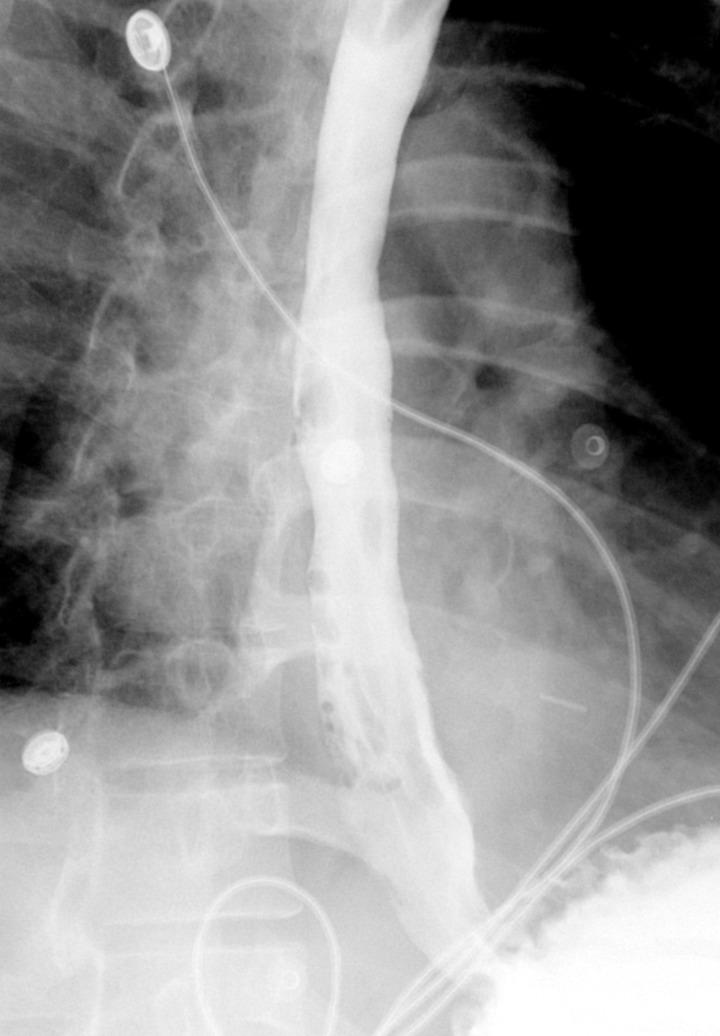

Eosinophilic esophagitis (EoE) is a rare disease of the esophagus that is characterized by eosinophilic infiltrate within the esophageal mucosa resulting in chronic inflammation and stenosis. It typically presents with symptoms of esophageal dysfunction with dysphagia and food impaction being the most common presenting complaints. Herein we describe a rare case presentation of a young patient with spontaneous esophageal perforation in the setting of undiagnosed EoE. We suggest that the placement of a covered esophageal stent can provide full closure of the perforation and restoration of the integrity of the GI tract without the need for more invasive open repair. The patient had a short recovery time with no reported postoperative complications upon 30 months follow up. We believe that it's important to consider and rule out EoE in patients with a history of dysphagia and esophageal perforation.

嗜酸性粒细胞性食管炎(EoE)是一种罕见的食管疾病,其特征是食管黏膜内嗜酸性粒细胞浸润,导致慢性炎症和狭窄。它通常表现为食管功能障碍的症状,吞咽困难和食物嵌塞是最常见的主诉。在此,我们描述了一例年轻患者在未诊断出EoE的情况下发生自发性食管穿孔的罕见病例。我们认为,放置带膜食管支架可以完全封闭穿孔并恢复胃肠道的完整性,而无需进行更具侵入性的开放修复。该患者恢复时间短,在30个月的随访中未报告术后并发症。我们认为,对于有吞咽困难和食管穿孔病史的患者,考虑并排除EoE很重要。